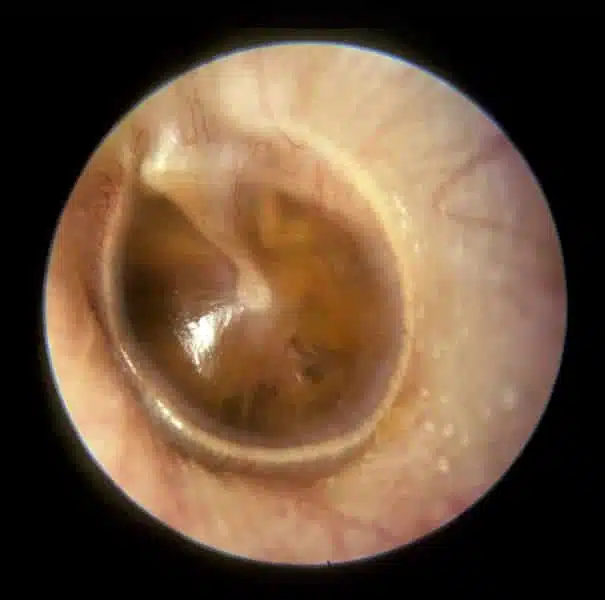

Otitis Media with Effusion

Tympanic membrane is retracted with prominence of handle of malleus which is more horizontal

Tympanic membrane may be bulging or have air fluid level behind

Yellow/amber appearance

Light reflex apparent